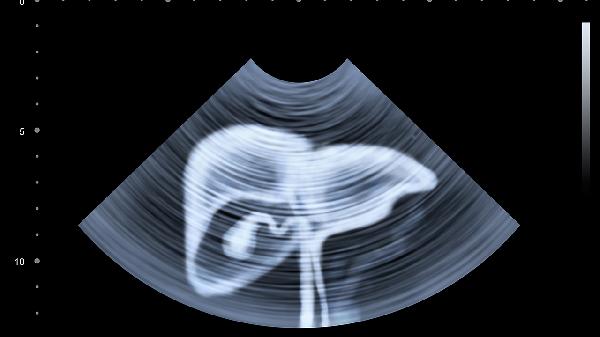

肝功能异常可能会导致腹胀。肝功能异常时,消化功能受到影响,胆汁分泌减少,胃肠蠕动减慢,容易引起腹胀。肝功能异常可能与病毒性肝炎、脂肪肝、肝硬化等因素有关,建议及时就医检查。

肝功能异常时,肝脏合成白蛋白的能力下降,血浆胶体渗透压降低,导致腹腔积液,从而引起腹胀。胆汁分泌减少会影响脂肪的消化吸收,未消化的脂肪在肠道内发酵产生气体增多,也会导致腹胀。肝脏代谢功能下降,体内毒素堆积,可能刺激胃肠道,引起胃肠功能紊乱,出现腹胀症状。

严重的肝功能异常如肝硬化失代偿期,门静脉高压导致胃肠道淤血,影响消化吸收功能,腹胀症状更为明显。肝功能异常还可能合并腹水、脾大等情况,进一步加重腹胀。部分患者因肝脏解毒功能下降,肠道菌群失调,产气增多,也会出现持续性腹胀。

出现不明原因腹胀时,建议及时检查肝功能,明确是否存在肝脏疾病。日常生活中应注意饮食清淡,避免高脂、高蛋白食物,适当补充维生素,限制钠盐摄入。保持规律作息,避免饮酒和滥用药物,定期复查肝功能指标。若腹胀持续不缓解或伴有黄疸、乏力等症状,需尽快就医治疗。